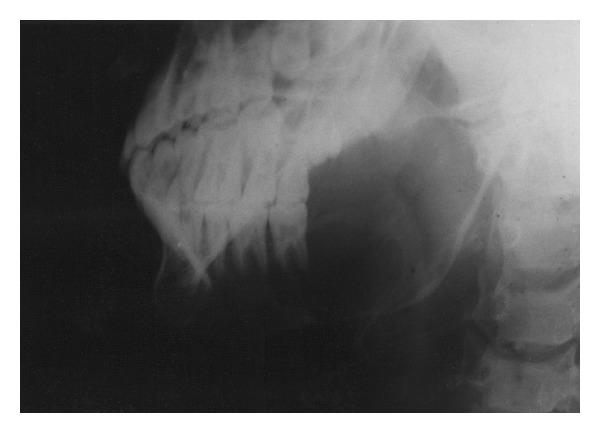

An aggressive and fatal case of osteosarcoma of the mandible in a 19-year-old female is reported. Six weeks after the clinical appearance of the swelling, the patient died. This paper is unique in that the age of occurrence and the biologic behavior of the tumor were not consistent with the reported literature. The case report is followed by a brief review of osteosarcoma of the jaw with a note on its clinical presentation, diverse radiologic appearance, varied histopathologic picture, and prognosis.

报告了一例19岁女性下颌骨肉瘤侵袭性致死病例。肿胀临床表现出现六周后,患者死亡。本文的独特之处在于肿瘤的发病年龄和生物学行为与已报道的文献不一致。病例报告之后是对颌骨骨肉瘤的简要综述,包括其临床表现、多样的放射学表现、不同的组织病理学图像及预后。